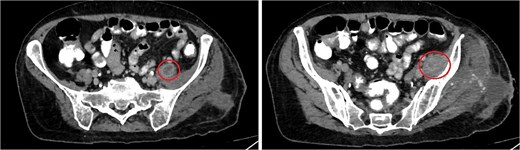

One week after the second stage DAIR, lab tests showed WBC 7500 (63% neutrophils), ESR 102, and CRP 48. CT abdomen and pelvis with IV contrast at 2 weeks did not show any intraabdominal collection or fistula suspicious of primary source of seeding, however it showed fluid collection in the left psoas muscle extending to the iliacus (8.7 × 2 × 1.5 cm), suggestive of deep abscess formation (Fig. 5) with superficial collection in vicinity of left proximal femur (Fig. 6). The latter collection was superficial and was drained at the bedside, releasing non-purulent fluid. The deep abscesses were drained by interventional radiology and a pigtail catheter was inserted for 1 week. Cultures from the deep collection grew K. pneumoniae susceptible to meropenem, which was used to replace ceftriaxone.

CT abdomen/pelvis showing rim enhancing fluid collection (marked with circle) in the left psoas muscle (left image) with extension to the left iliacus (right image) measuring 8.7 × 2 × 1.5 cm, suggestive of abscess formation.